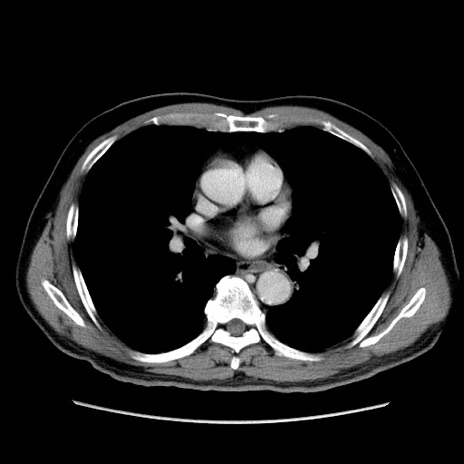

症例34(横断像)

【症例】60歳代 男性

【主訴】右鼠径部膨隆

【現病歴】1年程前より右鼠径部膨隆あり。自己にて還納可能だったため放置していた。3時間前より右鼠径部の脱出を認め、還納困難となり受診。

【既往歴】高血圧

【身体所見】右鼠径部に小児頭大の膨隆あり。弾性硬であり、用手還納は困難。左鼠径部にも膨隆を認める。脱出はなし。

【データ】WBC 15500、CRP 測定なし